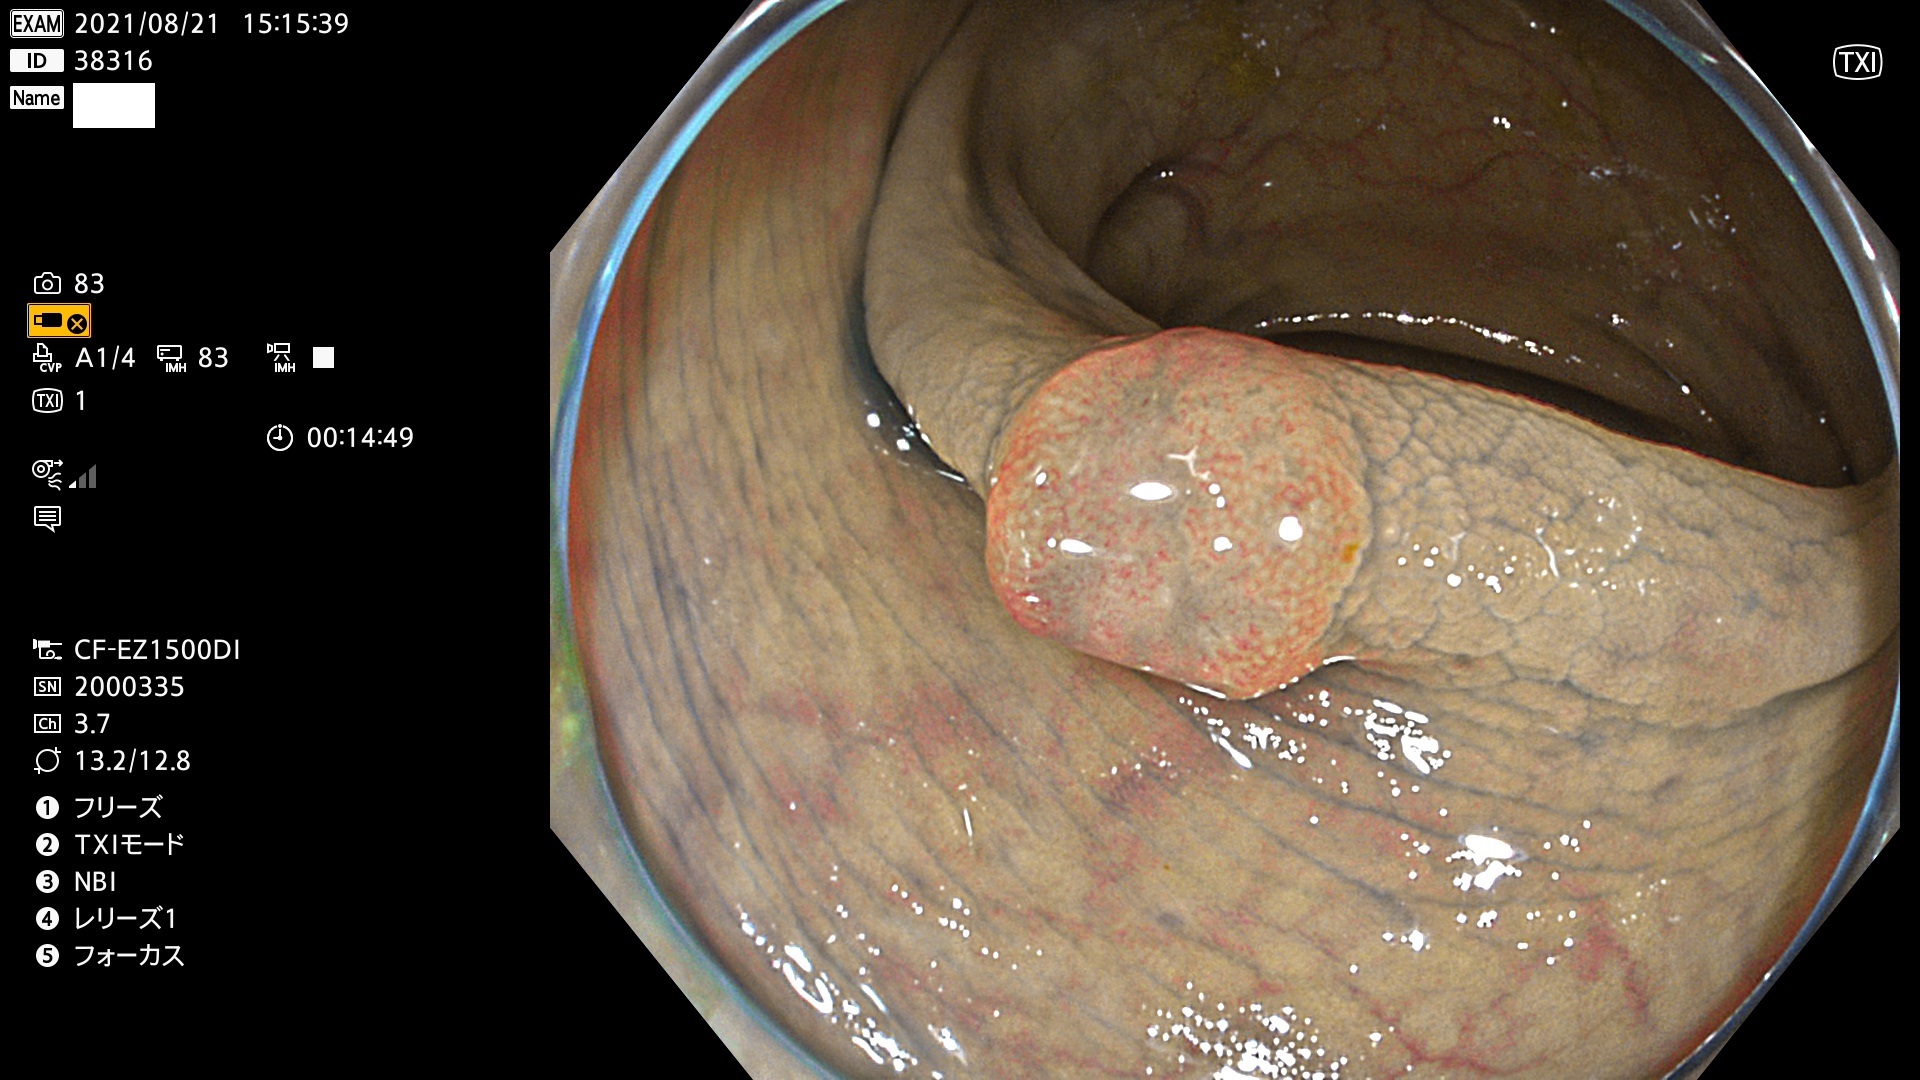

38300 38301 38302 38303 38304 38306 38307 38308 38309 38310 38311 38312 38313 38314 38315 38316 38317 38319 38321 38322 38323 38324 38325 38327 38331 38332 38333 38334 38337 38338 38339 38340 38341 38343 38346 38348 38349 38350 38351 38352 38353 38354 38355 38358 38359 38360 38361 38362 38363 38365 38366(SSAP) 38368 38369 38370 38371(SSAP) 38372 38374 38375 38376 38377 38378 38380 38381 38382 38383 38384 38385 38386 38388 38389 38391(SSAP) 38395 38397 38399

発見困難で危険性の高い平坦型病変(上記100名より抽出)